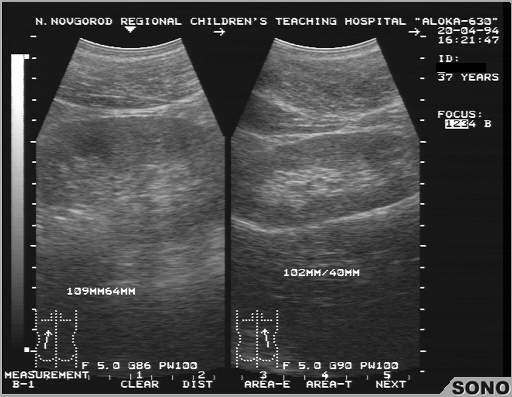

Умеренная гипоплазия левой почки